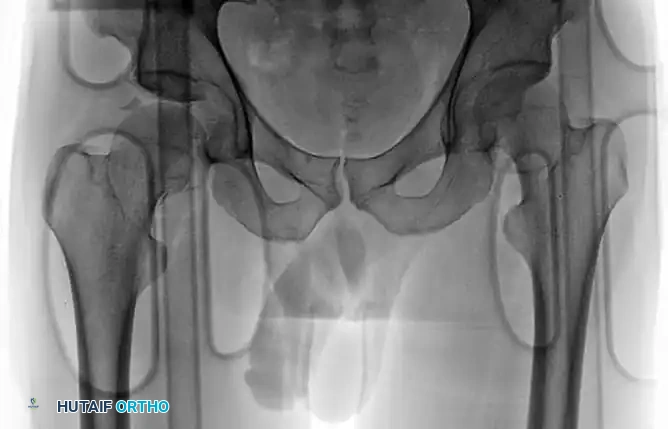

Patients with a pure posterior hip dislocation present with a highly characteristic lower extremity posture. Because the femoral head is displaced posterior and superior to the acetabulum, the limb is typically shortened, adducted, and internally rotated. The hip is usually held in a flexed position.

FIGURE 55-52 B: Anterior view of the characteristic extremity posture.